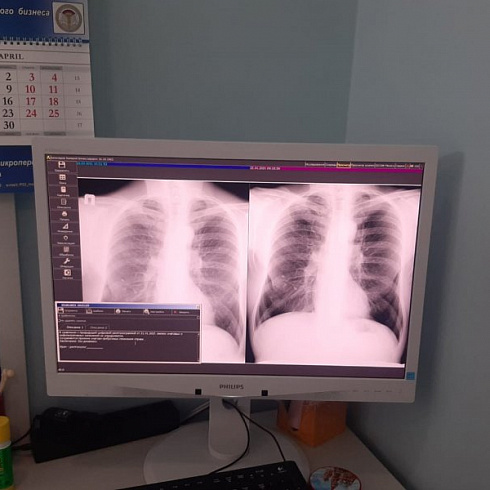

До 26 марта каждый желающий может без направления обратиться в противотуберкулезный диспансер и пройти флюорографическое исследование, спирографию, экспресс-тестирование на ВИЧ-инфекцию, получить консультацию детского или взрослого фтизиатра. Детям могут сделать манту или диаскинтест.

«Пациенты участвуют в этой акции очень активно. Я приехал на работу к 8 утра, и уже было много желающих пройти обследование. Севастопольцы достаточно активно и внимательно относятся к своему здоровью и пользуются возможностью проверить здоровье без записи к специалисту», — рассказал главный врач противотуберкулезного диспансера Андрей Вербицкий.

Противотуберкулезный диспансер работает с 8 до 18 часов. Детей принимают до 14 часов, взрослых и подростков — до конца рабочего дня. С собой необходим только документ, удостоверяющий личность.